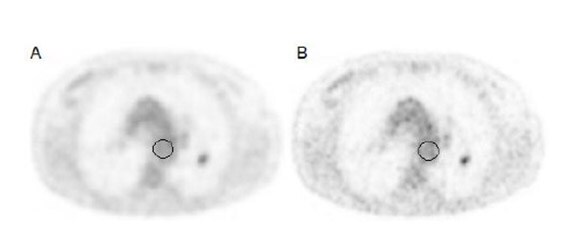

Figure 1: F18-FDG PET images using standard voxel reconstruction (A) and small voxel reconstruction (B). The lesion in the left lung (volume 0.68 mL) with a SUVmax of 2.6 using the standard voxel reconstruction, increased by 54% to 4.0 using the small voxel reconstruction. The SNRmax increased by 115% (from 3.1 to 6.6). The ROIs used for background measurements are illustrated by the black circles.